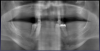

Fig 5. The patient’s decisions were based on her socioeconomic situation 10 years prior.

Figure 5

Patients seeking more comfort, better retention, and confidence from implant-retained complete dentures may choose narrow-diameter dental implants in the mandibular arch, primarily making this decision based on the lower fees for mini-implant services.15 Figure 4 and Figure 5 depict a common scenario of a maxillary complete denture opposing an implant-supported (mini-implant) complete denture. Ten years prior, the patient chose to have her mandibular arch treated with narrow-diameter implants and a mandibular removable overdenture. Figure 5 shows significant bone loss and soft-tissue recession around the narrow-diameter implants. The mini-implants serviced the patient well for 10 years but left her with a greater challenge and cost to restore the mini-implants with a new prosthesis. The dentist needed to re-engineer a means for retention other than the current ball and o-ring attachments. Over time the overdenture housings and o-ring assembly created a deformation of the ball shape of the mini-implants, decreasing the retentive nature of the o-ring and ball attachment properties. Ten years of mastication and metal-on-metal lateral movement contributed to this deformation. At 87 years old, this patient did not want to undergo additional surgical implant therapies and was looking for an alternative. The mini-implants still were able to service her. An alternative treatment option requires a cast or a milled retention bar to splint the remaining implants and development of a removable overdenture that will be retained by prefabricated attachments.